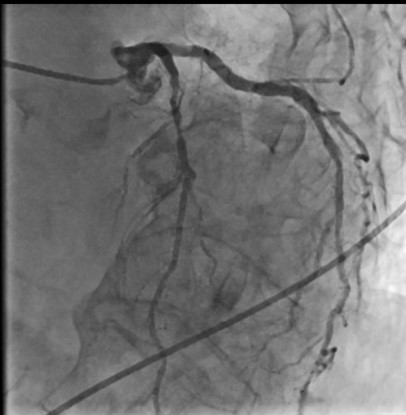

Relevant Catheterization Findings

CACAG showed TVD without significant LM stenosis (90 % stenosis of prox-to-mid LAD, 70 % of DG1, 80 % of ostial LCX, 70 % of dis LCX, 90 % of mid RCA and 70 % of PDA). Consequently, the Heart Team's decision, lesion preparation and IVUS-guided stents implantation were completed for the mid RCA and prox-to-mid LAD. The patient was scheduled for TAVR on the next day. On that morning, she developed hematochezia with stable vital signs and hemoglobin. So, the TAVR was proceeded.